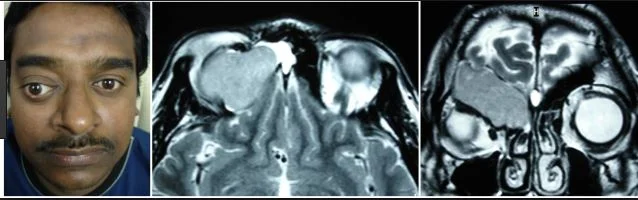

In this case the mucocele was in the maxillary sinus but they can occur in the frontal sinus and extend into the orbit, the ethmoid sinus compressing the optic nerve, and the sphenoid sinus compressing the pituitary and brainstem or causing cavernous sinus thrombosis.  Two thirds of all mucocles occur in the frontal and ethmoid sinuses.  Mucoceles are rare in the pediatric population except in cystic fibrosis. The mucocele below is in the frontal sinus and causing proptosis.